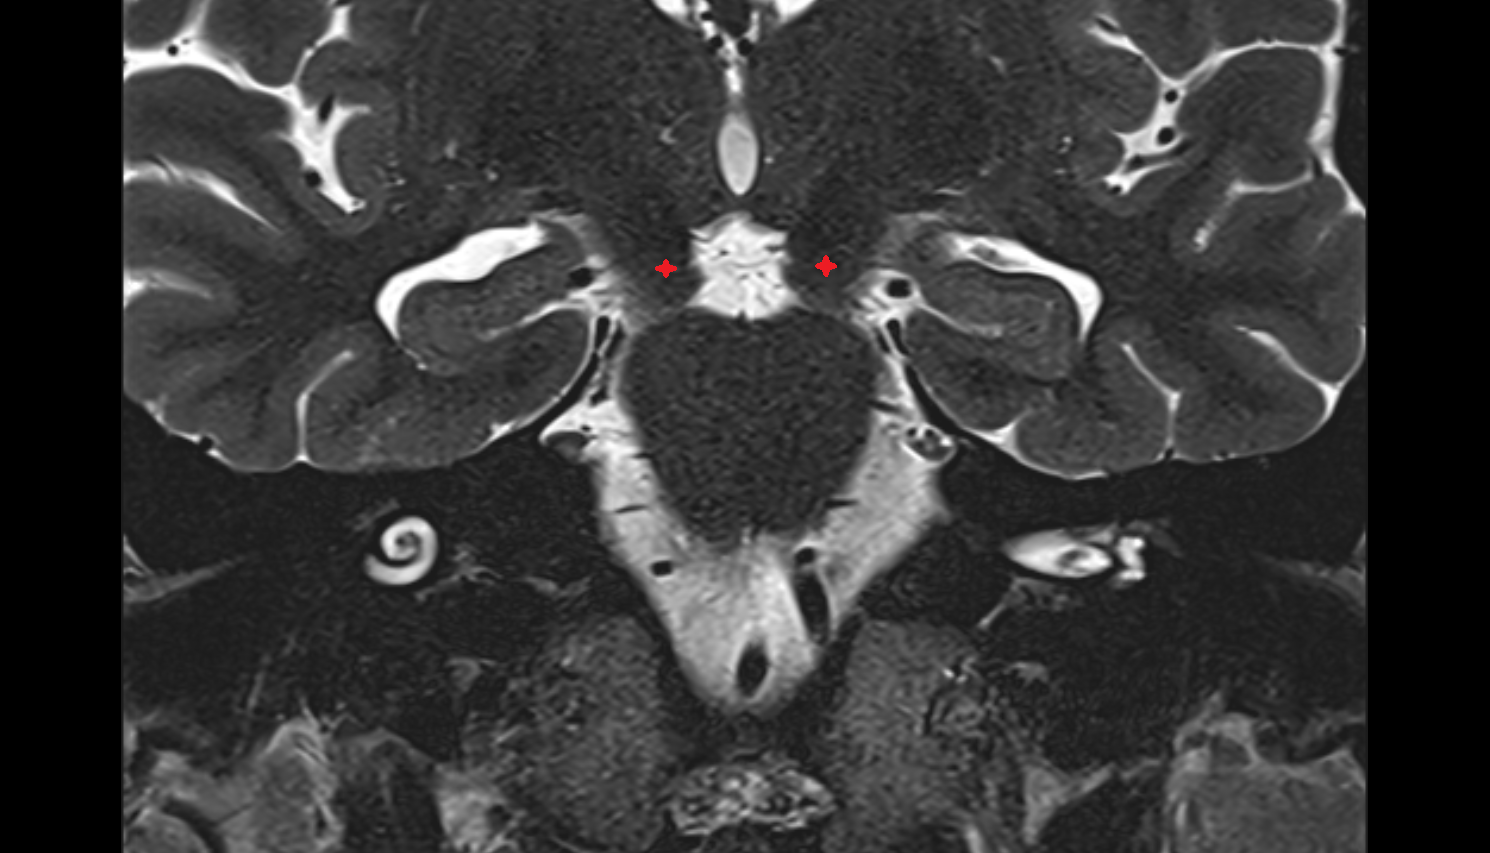

- Lateral aperture of fourth ventricle (foramen of Luschka)